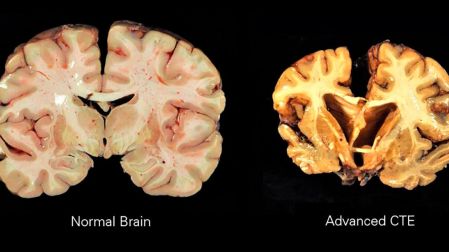

Clínicamente esta afectación es conocida como CTE o encefalopatía traumática crónica, una enfermedad neurodegenerativa provocada por la acumulación de traumas cerebrales que genera demencia, pérdida de memoria, depresión, agresividad y confusión.

La autopsia demostró que padecía de Encefalopatía traumática crónica, (CTE), misma enfermedad que desde 2007 comenzó a invadir al fútbol americano profesional de los Estados Unidos y que la NFL le ha costado trabajo admitir.